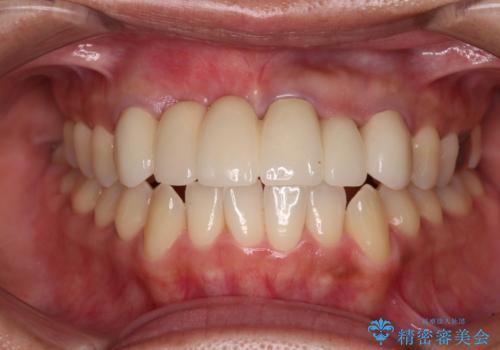

1回の歯肉移植により歯肉の厚みは大幅に改善されましたが、折角なのでもう少し大きくしたいとの要望があり、2回目の処置も行うこととしました。

厚みも高さも十分な歯肉量を獲得することができました。